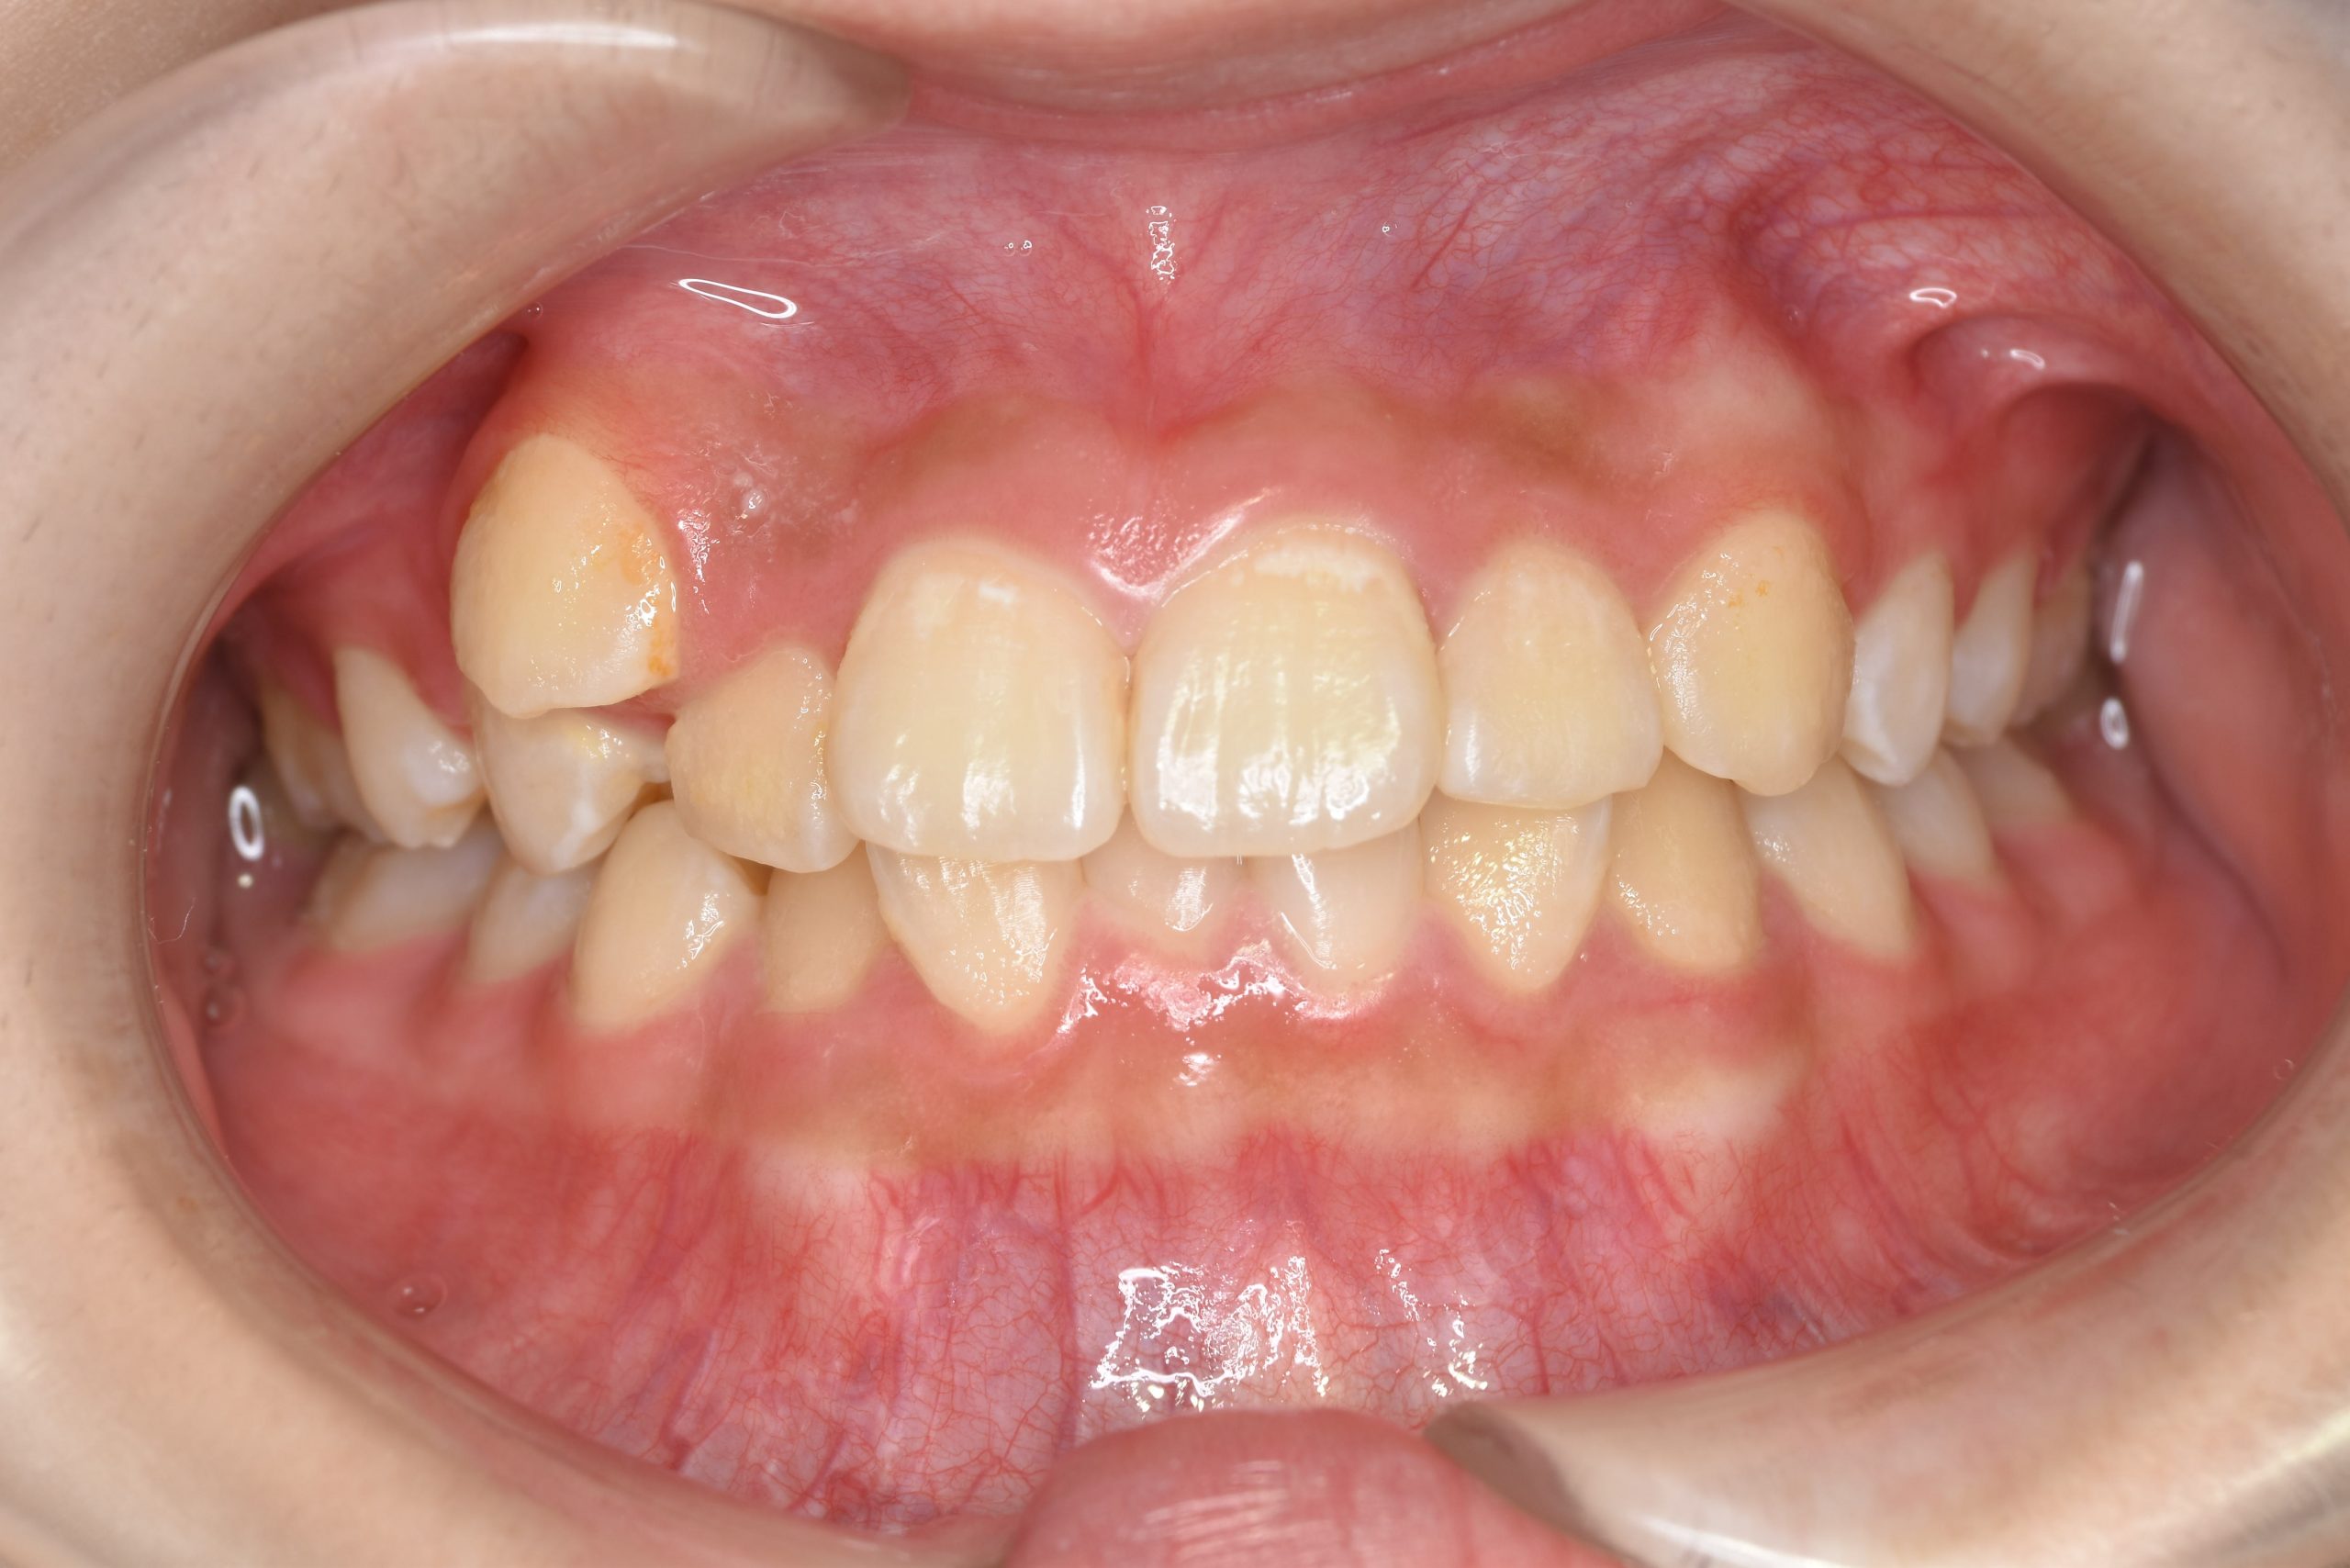

主訴 中心から前歯がずれている

施術内容 成人矯正1期治療

治癒期間 1年3か月間

費用 954,800円(税込)

リスク・副作用 違和感、不快感、痛み